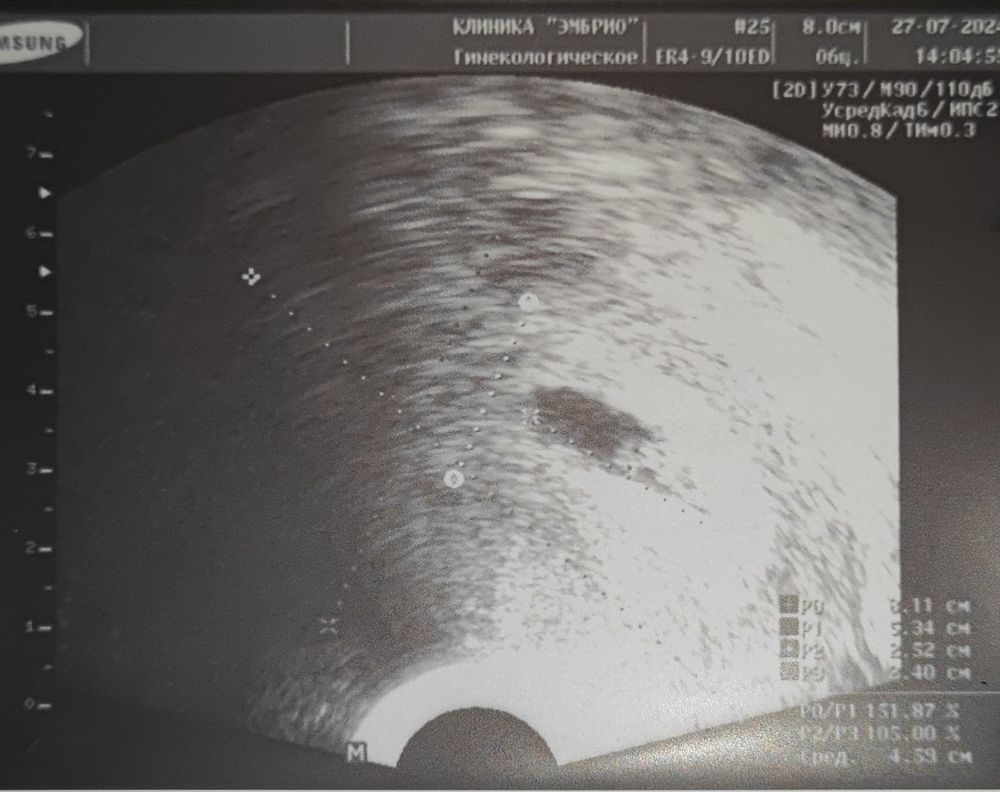

33 дпп 7 недель

Результаты УЗИВсем привет, сходила на второе УЗИ. ПЯ 17 мм, ЖМ 4.3, КТР 8мм.СБ+ больше 140 уд/мин. Видели на экране как бьётся сердечко, крошечная пульсирующая точка.